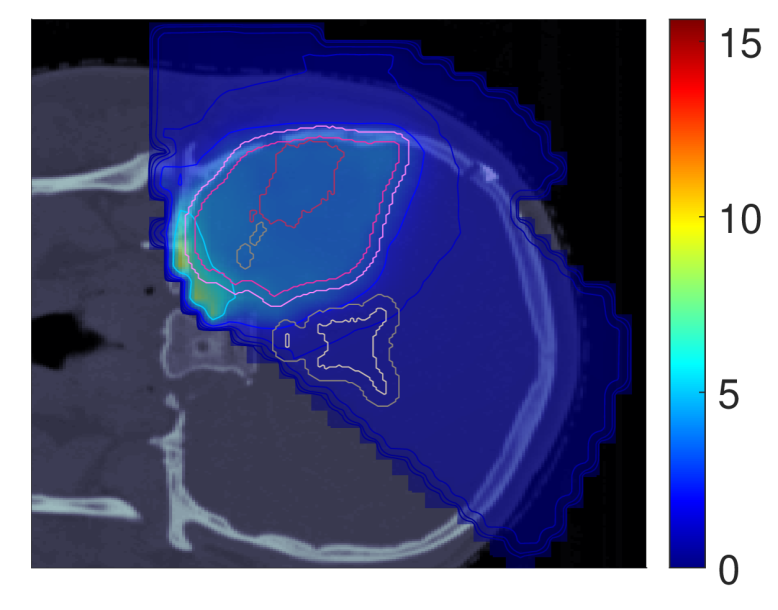

Figure 2 shows the optimal slice images of the dose (left), dose-averaged LET (middle) and POLO distribution (right). On the underlying CT scan, the tumor volumes are marked by violet to purple contours, while the VS (ventricles and 4 mm4\text{\,}\mathrm{mm} fringe) is outlined in white and gray. We observe the high-dose region covering all of the GTV, with a largely homogeneous transition to the clinical and planning target volumes (CTV, PTV), and a moderate to severe overlap to the VS. The dose-averaged LET distributes in layers, with increased values around the contour edge of CTV/PTV and local peaks at the distal ends of the proton beams. Accordingly, hot spots on the POLO map are found in regions where dose and dose-averaged LET scale up, or close to the VS. Beyond the PTV, the POLO map reveals cold spots, due to the steepness of the dose and dose-averaged LET gradients.

dRBE,fxd_{RBE,fx}ABCD ldl_{d}ABCD ppABCD

Refer to caption Refer to caption Refer to caption

NTCP:45.59 %NTCP:$45.59\text{\,}\mathrm{\char 37\relax}$ABCD

Figure 2: Optimal 2D slice images of the RBE-weighted fractional dose dRBE,fxd_{RBE,fx}, the dose-averaged linear energy transfer ldl_{d} and the probability function values pip_{i} for the baseline plan. The dose distribution (left) shows high target coverage with decreasing exposure beyond the CTV/PTV margins, but also visibly overlaps with parts of the VS. Meanwhile, for the dose-averaged LET (middle), layered homogeneity in the target volumes and local maxima at the distal ends of the proton beams can be observed. This results in more pronounced levels of POLO values within the target volumes, particularly in the presence of local dose-averaged LET maxima and in the environment of the VS. Referring back to the POLO model from Equation 1 and (3), we can expect exactly this type of coherence between the model output, the physical input feature profiles and the increased local risk near the VS. The baseline treatment plan exhibits a complication risk of 45.59 %45.59\text{\,}\mathrm{\char 37\relax} after evaluation of the POLO distribution with NTCPpNTCP_{p}.